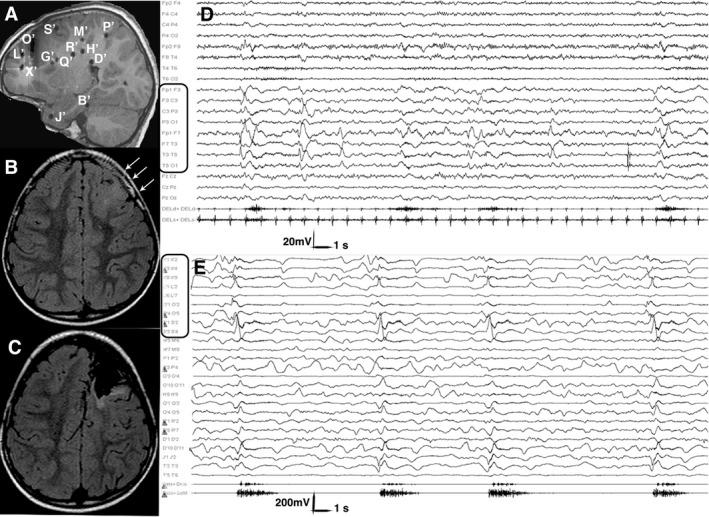

We retrospectively studied 80 children (aged 1.3 ± 2 years at seizure onset; 5.8 ± 4 years at surgery, 11.7 ± 5.7 years at last follow up). Magnetic resonance imaging (MRI) revealed structural abnormalities in 77/80 patients (96.3%; unilateral in 69: 89.6%). We performed invasive recordings in 24 patients (30%). In 21 patients in whom MRI or histopathology detected a lesion, electrodes exploring it constantly captured initial ictal activity at spasm onset. Fifty-eight patients (72.5%) underwent unilobar and 22 (27.5%) multilobar or hemispheric procedures. At last follow-up, 49 patients (61.3%) were in Engel class I. Multivariate logistic models showed completeness of resection of the seizure onset zone (OR = 0.016, 95%CI: 0.002, 0.122) and of the MRI visible lesion (OR = 0.179, 95% CI: 0.032, 0.999) to be significantly associated with Engel class IA outcome. Unfavorable outcome was associated with an older age at surgery, when it reflected a longer duration of epilepsy (OR = 1.383, 95% CI: 0.994,1.926).

Data emerging from invasive recordings and the good seizure outcome following removal of discrete epileptogenic lesions support a focal cortical origin of spasms. In patients with discrete epileptogenic lesions, the pragmatic approach to surgery should follow the same principles applied to focal epilepsy favoring, whenever possible, unilobar, one-stage resections.

我们回顾性研究了80名儿童(癫痫发作起始时年龄为1.3±2岁;手术时年龄为5.8±4岁,末次随访时年龄为11.7±5.7岁)。磁共振成像(MRI)显示80例患者中有77例(96.3%)存在结构异常(69例为单侧异常:89.6%)。我们对24例患者(30%)进行了侵入性记录。在MRI或组织病理学检测到病变的21例患者中,探测病变的电极在痉挛发作时持续捕捉到初始发作期活动。58例患者(72.5%)接受了单叶手术,22例(27.5%)接受了多叶或半球手术。在末次随访时,49例患者(61.3%)处于恩格尔I级。多变量逻辑模型显示,癫痫发作起始区的切除完整性(OR=0.016,95%CI:0.002,0.122)和MRI可见病变的切除完整性(OR=0.179,95%CI:0.032,0.999)与恩格尔IA级转归显著相关。不良转归与手术时年龄较大有关,这反映癫痫病程较长(OR=1.383,95%CI:0.994,1.926)。

侵入性记录得出的数据以及切除离散性致痫病变后良好的癫痫发作转归支持痉挛的局灶性皮质起源。对于有离散性致痫病变的患者,手术的务实方法应遵循适用于局灶性癫痫的相同原则,尽可能采用单叶一期切除。